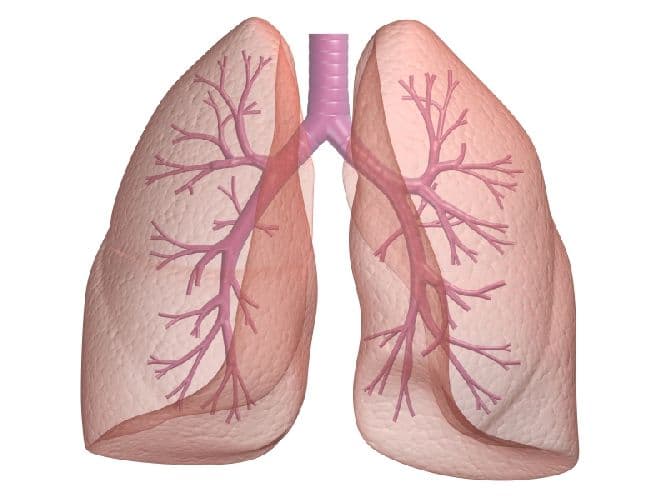

- Легкие

С помощью этого органа человек может дышать. Он похож на две светло-розовые губки, состоящие из миллиона крошечных пузырьков. Во время вдоха легкие расширяются, наполняясь воздухом. В это время кислород поступает в кровь и разносится по всему организму, а углекислый газ, в свою очередь, из крови попадает в легочные пузырьки и при выдохе выходит наружу. Так происходит процесс дыхания.

Рис. 3. Легкие.